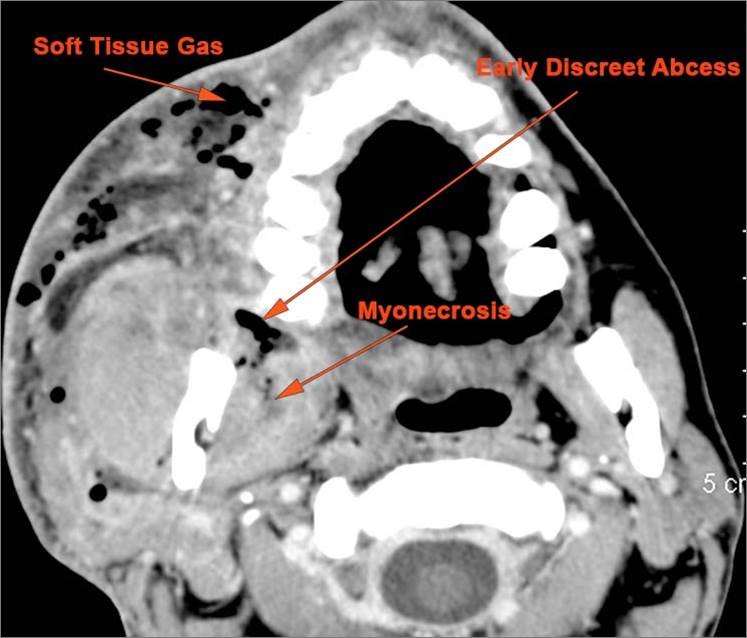

There is general or localized soft tissue swelling of the superficial or deep neck soft tissues. [Yes/No]

There is gas in the soft tissues. [Yes/No]

There is excessive enhancement or thickening of the fat or other soft tissues within or surrounding the buccal space, masticator space, floor of the mouth, submandibular space or the adjacent superficial fascia or subcutaneous fat and skin. [Yes/No]

There is subperiosteal abscess or an abscess cavity adjacent to or involving the maxilla or mandible. [Yes/No]

Odontogenic, Buccal-Masticator, FOM Infections

Odontogenic/masticator space/buccal space infection [with/without] abscess.